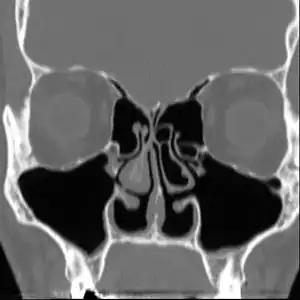

| Altered nasal anatomy after bilateral subtotal inferior turbinectomy. | |